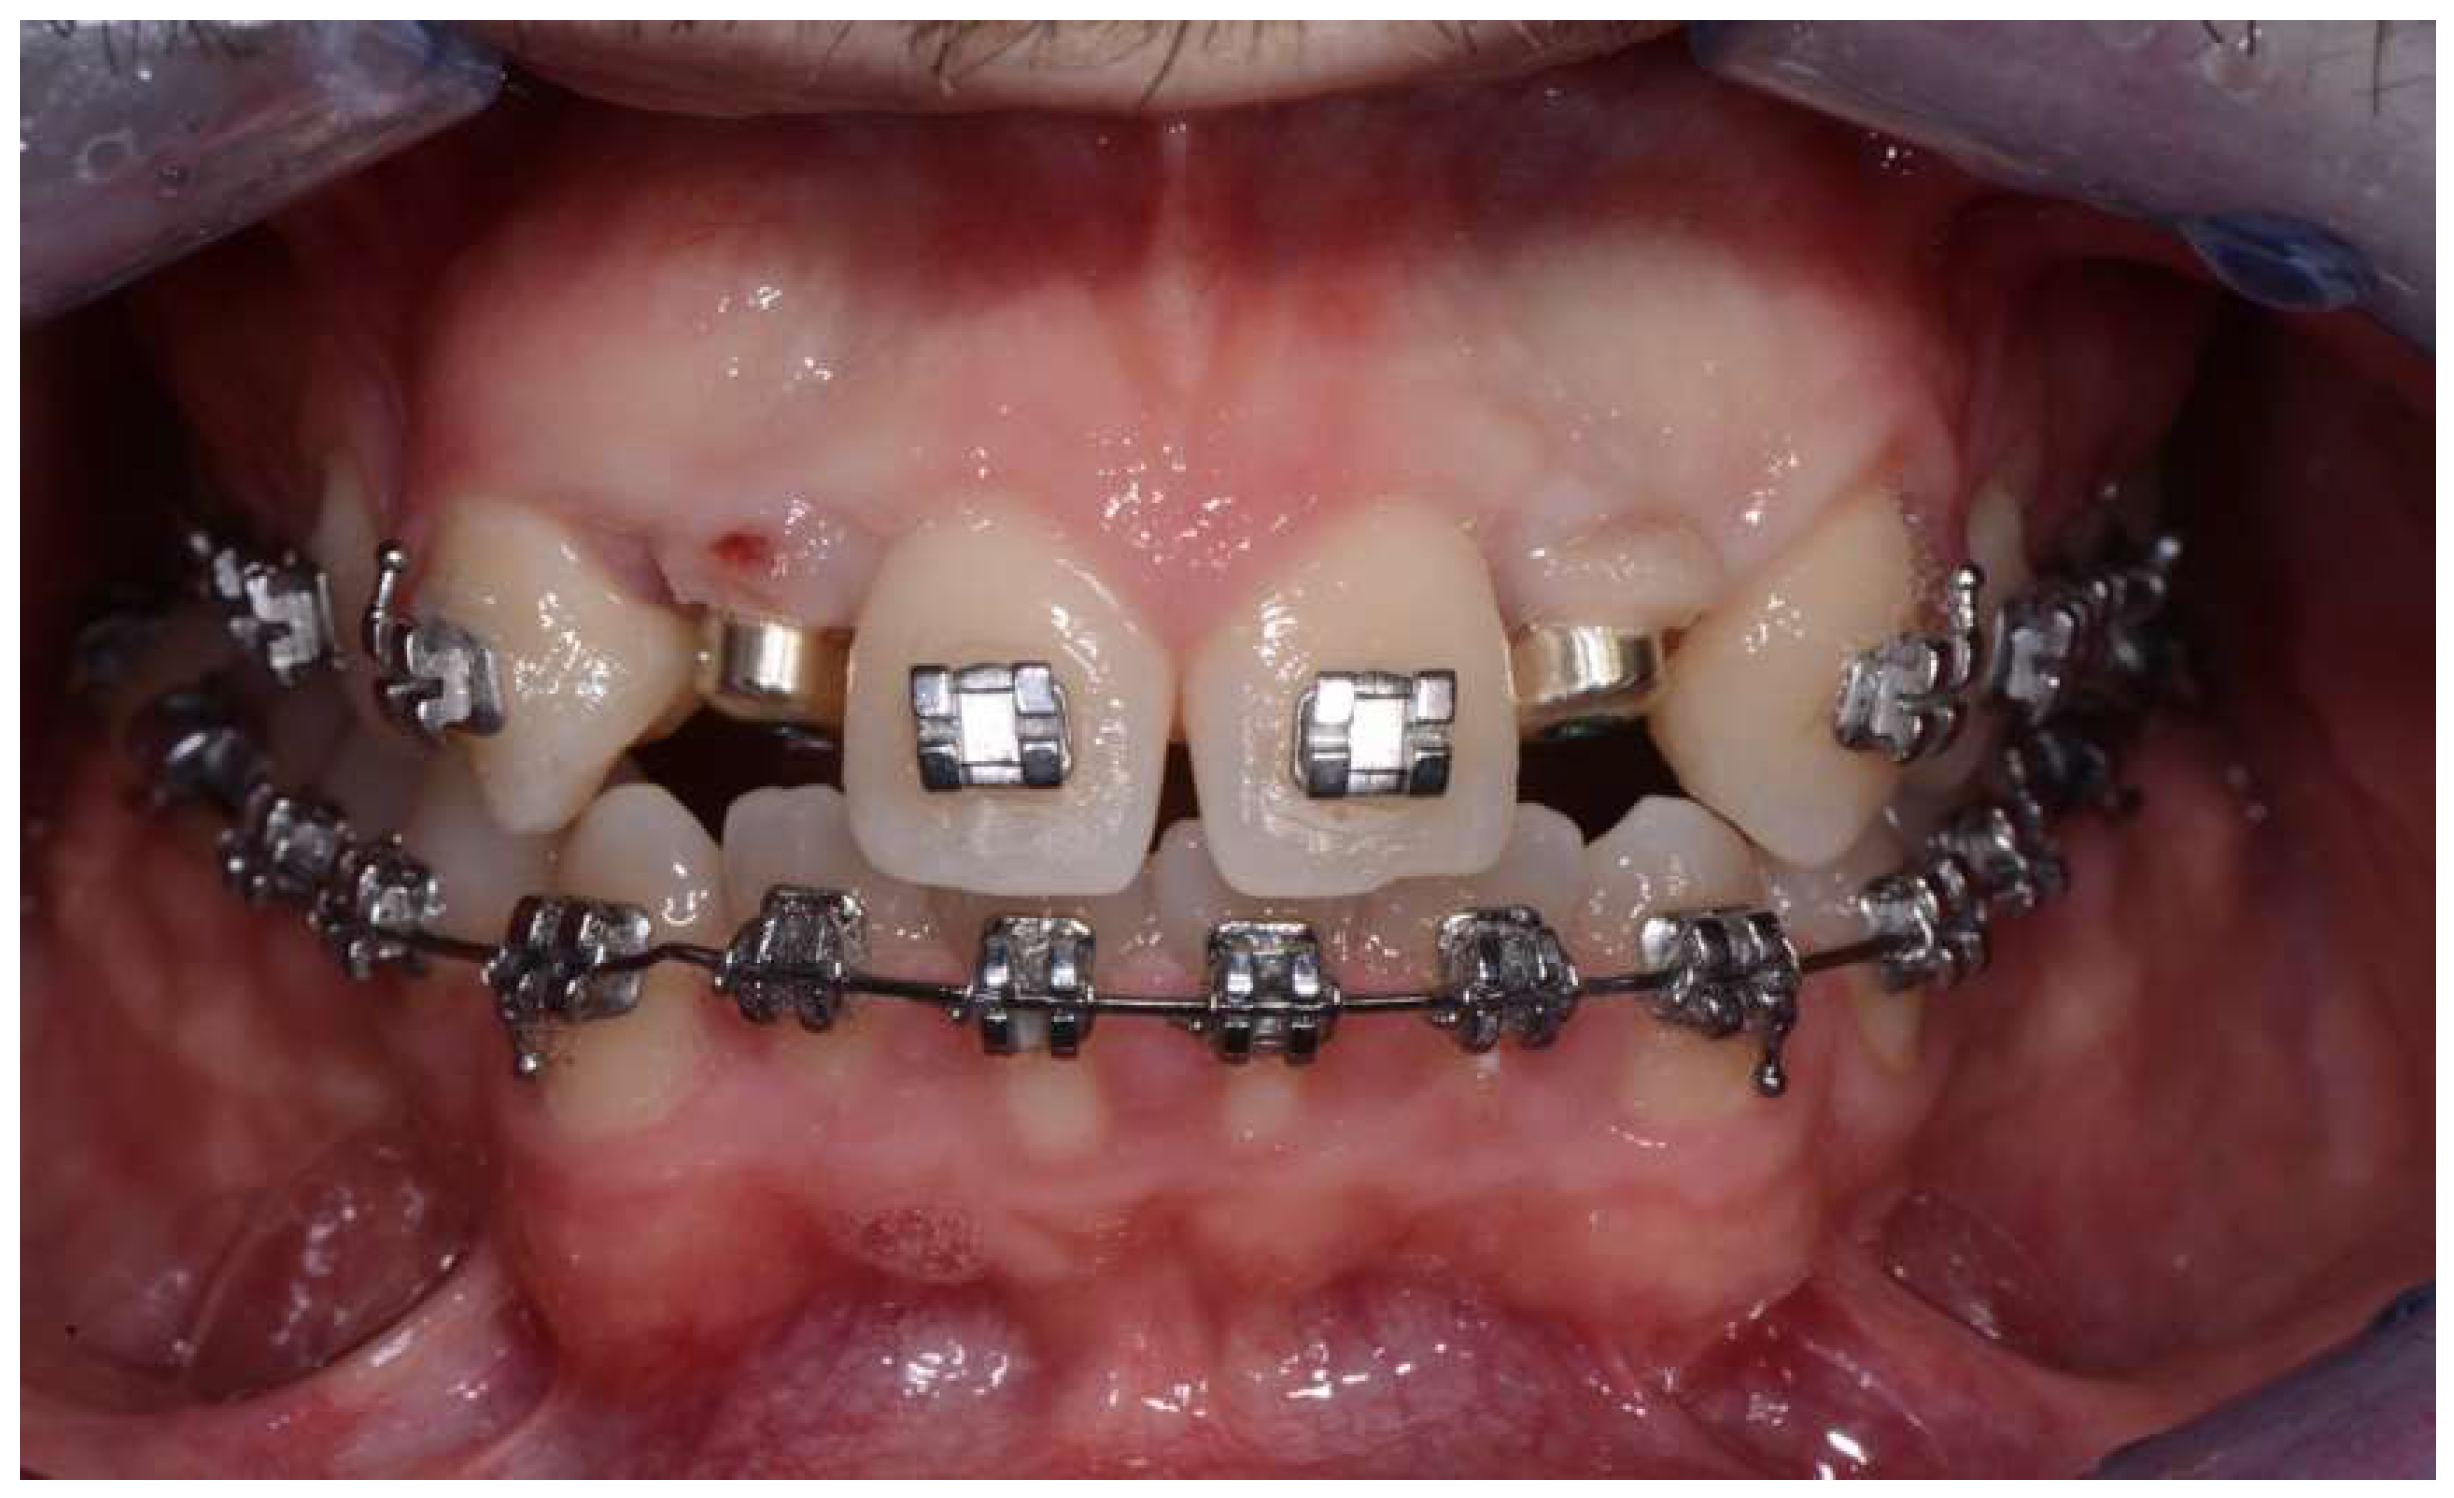

2. Materials and Methods

- 4–10 months: periodontal and orthodontic preparation (if necessary) and implant surgery;